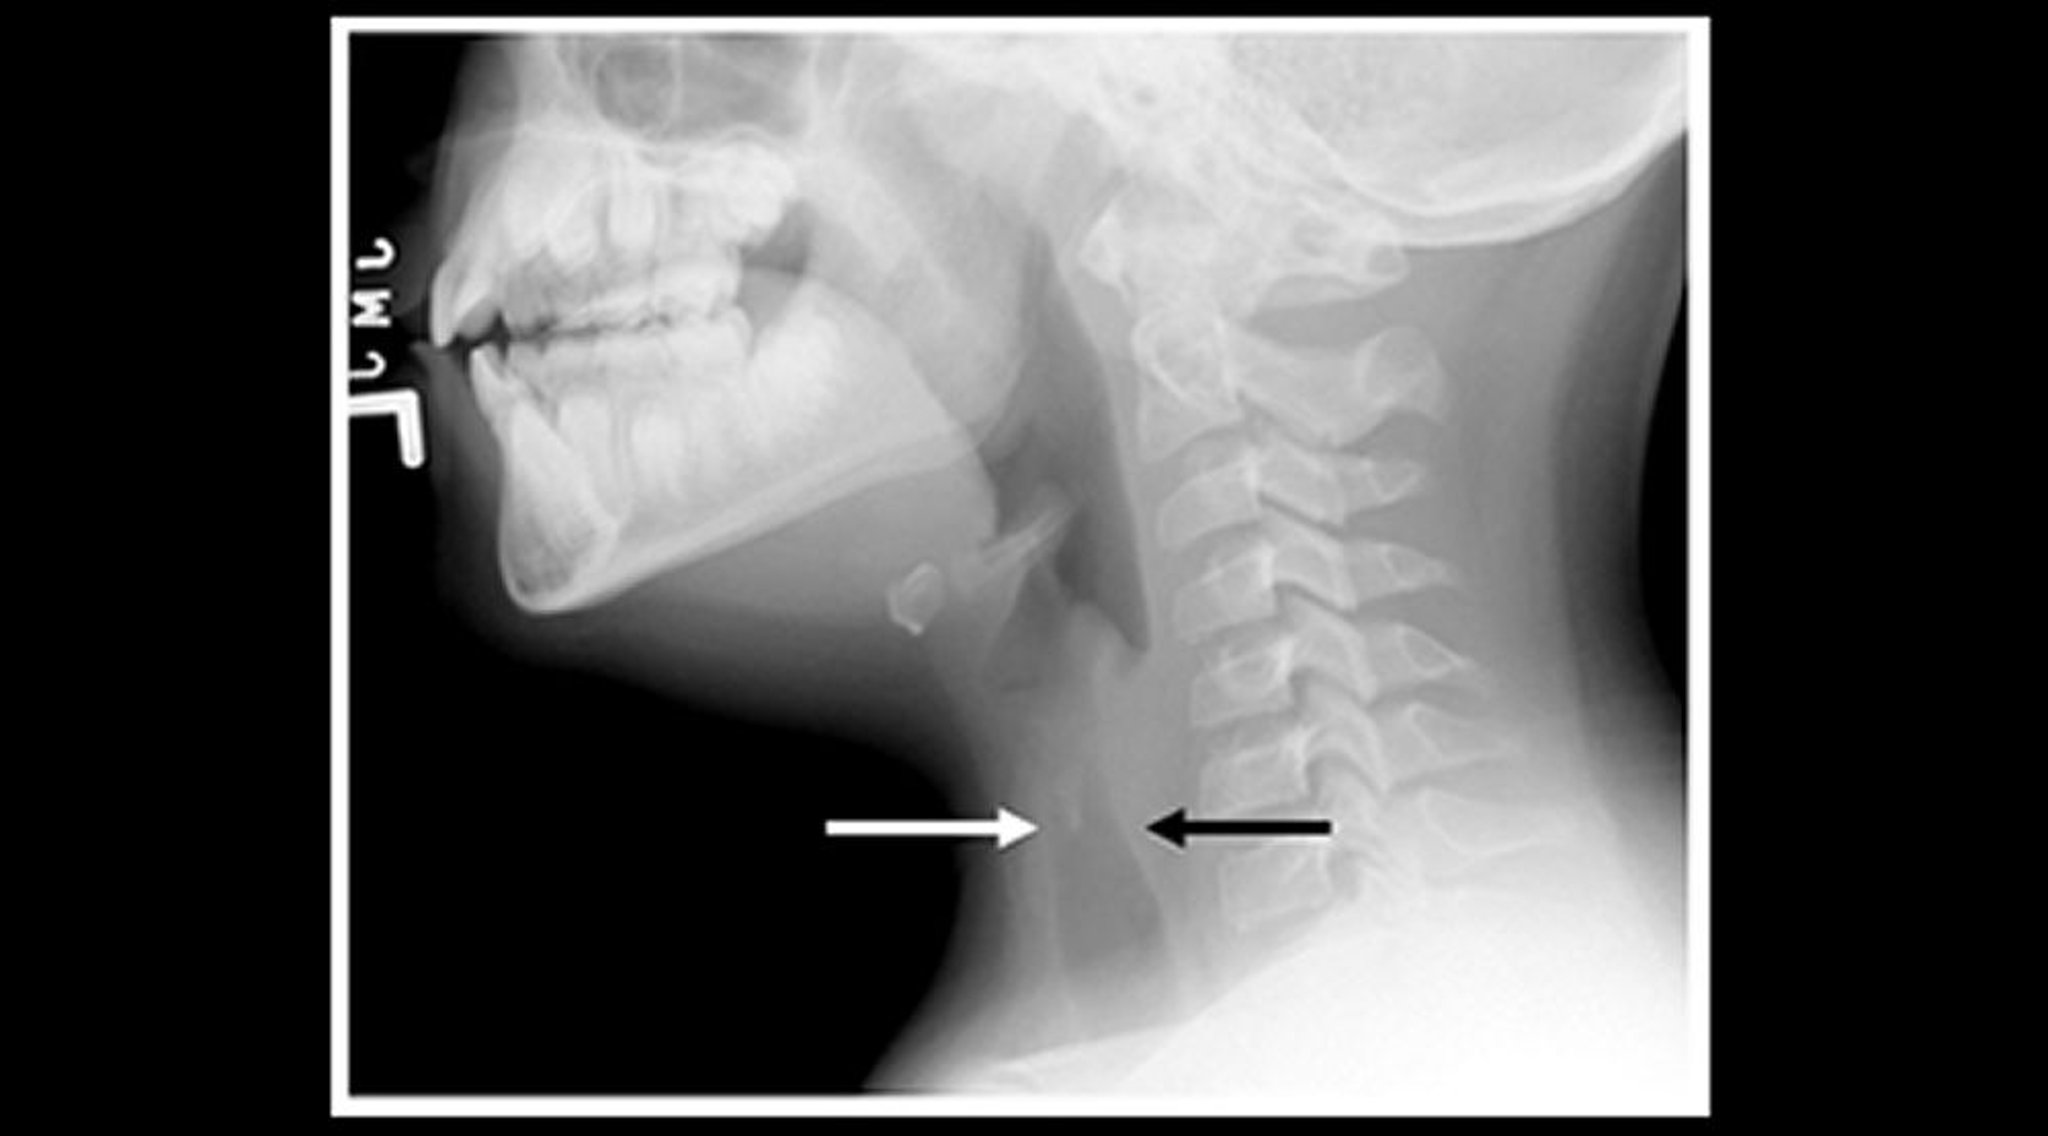

Phim X quang của một trẻ bị viêm thanh khí phế quản (ảnh đứng dọc)

Phim X quang phần mềm ở cổ của một trẻ bị viêm thanh khí phế quản cho thấy bóng khí khí quản dưới thanh môn thu hẹp (mũi tên) và giãn các khoang khí ở hầu.

Hình ảnh do bác sĩ John McBride cung cấp.